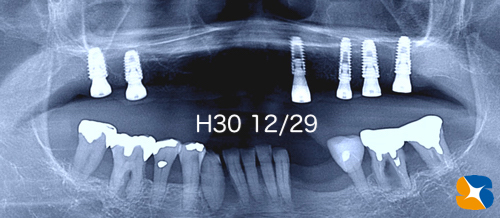

今年 1/25 のブログ「上顎の天井裏を人工骨で埋立て〜再建」の経過報告

カテゴリ:Dr.鈴木日記 インプラント 静脈麻酔鎮静法

上顎の天井裏を人工骨で埋立て〜再建の経過報告です。

8ヶ月前、インプラント移植が不可能だった骨を増殖させる手術を行いました。

その後、CTで骨の状態を確認したうえで、以下のインプラント移植手を9月に行いました。

〈骨の厚み増加に成功〉

①側面から観たCT画像断面

②正面から観たCT画像断面

③頭上から観たCT断層写真

使用インプラント:USAオッセムSA 直径5㎜と6㎜、長さ10㎜

想像以上に骨がガッチリと出来上がっていました。

手術から3ヶ月後の様子です。

手術から4ヶ月後の様子です。

昨年12/29のブログ「永年の夢に向かって …最後を飾るインプラント」の結果報告

カテゴリ:Dr.鈴木日記 インプラント 歯科全般 静脈麻酔鎮静法

〈Before〉

上アゴの骨が痩せ細り、インプラントも無理だと諦め、永年、入れ歯で苦労されてきた患者様のその後の結果をお知らせします。

〈New〉

12月28日、今年最後のインプラント施術。76歳の女性。主訴は「総入れ歯でご飯を食べていても全く美味しくないし、うっとしい。もう嫌になる。永いこと、アワビやタコやたくわんを食べていない。インプラントも考えていたが、骨が無いので断られた経験がある。それにとっても怖がり。どうしたもんですかね?」でした。

CT画像の分析を徹底的にした結果、僅かに残された骨の厚みと高さのある部分に、6本のインプラントを移植することが出来ました。